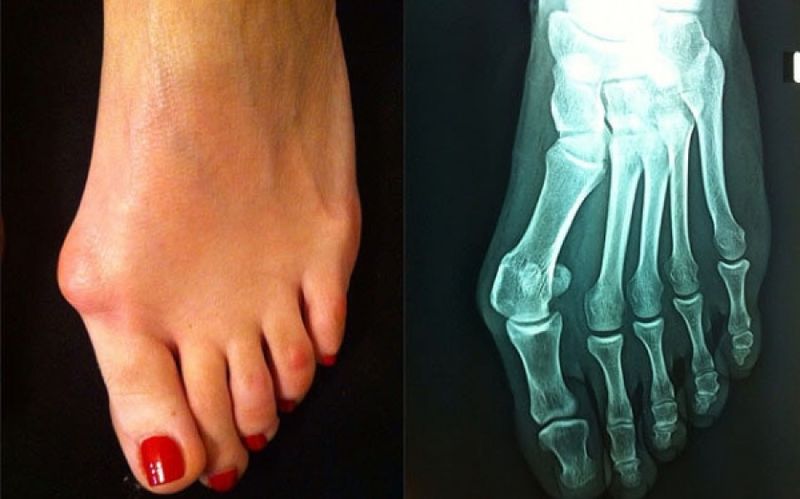

Το κότσι (Βλαισός Μέγας Δάκτυλος) είναι η πιο συχνή παραμόρφωση που δημιουργείται στη βάση του μεγάλου δακτύλου στο πόδι. Πρόκειται για παραμόρφωση της μεταταρσιοφαλαγγικής άρθρωσης και το βασικό πρόβλημα είναι η δημιουργία κάλου στην έσω πλευρά του ποδιού και η προς τα έξω παρέκκλιση του μεγάλου δακτύλου. Παρέκκλιση άνω των 15-20° θεωρείται παθολογική.